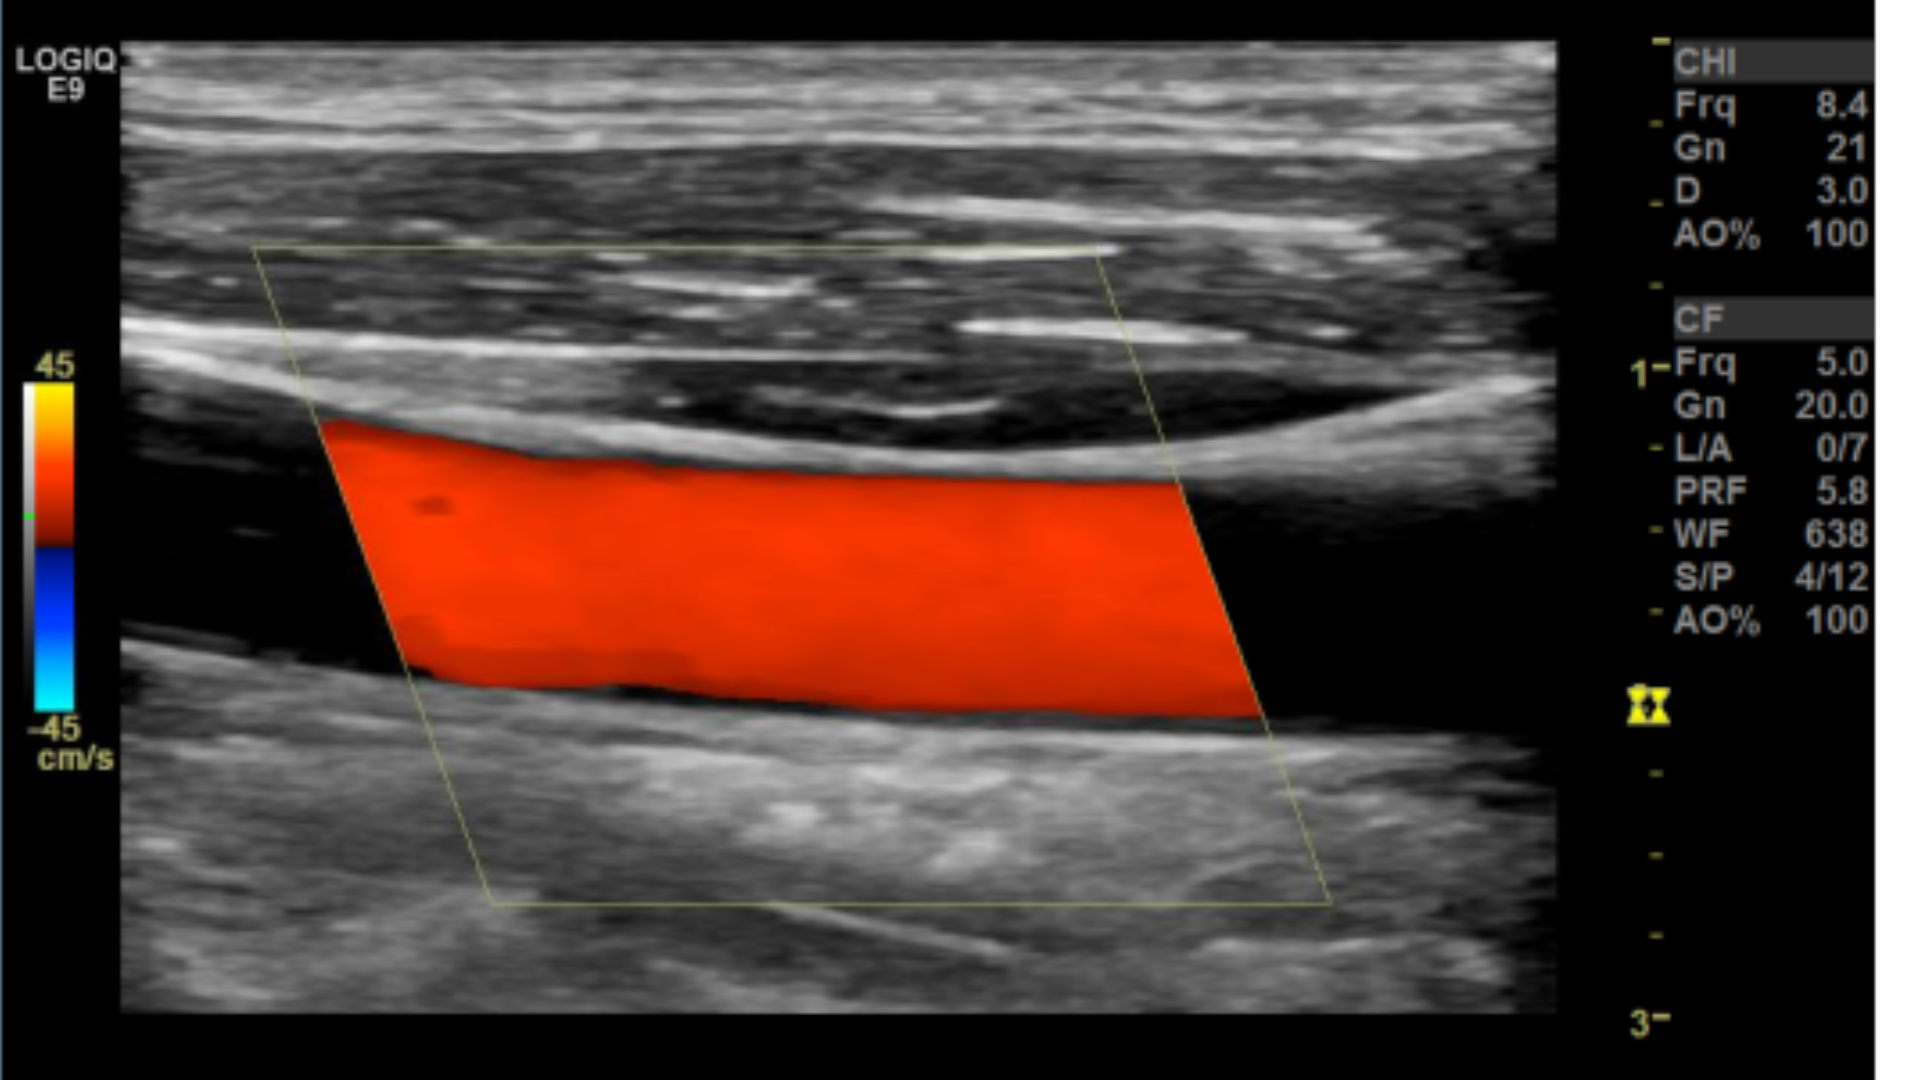

Taking technically superior images not only looks aesthetically pleasing, it is important in that it provides accurate data to render a correct diagnosis. A few parameters you may want to tweak are the doppler scale or pulse repetition frequency PRF and gain for both color and spectral doppler.

Scale/PRF too high

Optimal Doppler settings